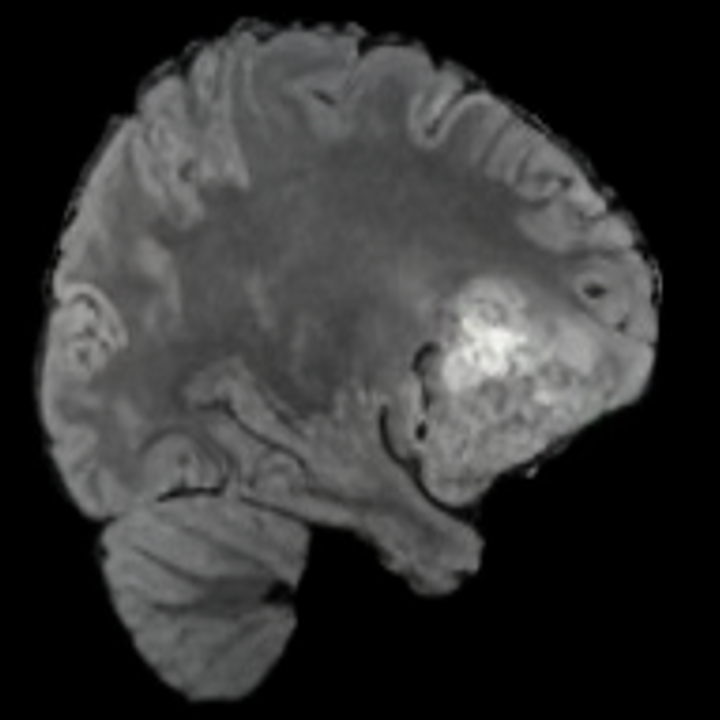

Our results unequivocally highlight the superior performance of X-Diffusion in terms of both qualitative and quantitative metrics. Representative MRI volumes generated by our pipeline, when juxtaposed with ground-truth images, showcased remarkable similarity, with even intricate physiological features like tumor information, spine curvature, and fat distribution being accurately captured.

Notably, X-Diffusion achieves sota dB for a few input slices while baselines require more than 60 input slices to achieve similar performance (Figure 7). The margin is more than 12 dB PSNR for the 1-slice input in both the BRATS and the UK Biobank benchmarks (see Table 1 and Figure 6). For reference, two randomly sampled MRIs from the UK Biobank would have a PSNR of 15.95 dB 0.36 (on 4800 randomly sampled examples). The slices from 3D reconstructed volumes at varying depths and axis of rotation visually match the ground truths (see Figures 5 and Figure 4). We also plot the error map (Figure 4) of such X-Diffusion generations to highlight the differences with the ground truth MRIs.

Tumour Information Preservation. For the brain tumor segmentation, we use a Swin UNETR model[27, 70], trained with random rotation, and intensity as data augmentation. In Figure 5, we highlight the tumor profiles of the generated MRIs compared to the ground truth tumour profile. In the test set with human ground-truth annotations (), the real MRI Dice score is 85.15 while the generated MRIs from a single slice have a dice score of 83.09. This shows how the generated MRIs indeed preserve the tumor information and can act as an affordable and informative pseudo-MRI, before conducting an actual costly MRI examination in hospitals.